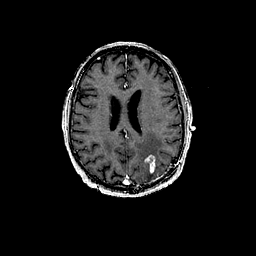

Glioma overlay -- Slice #74

[Home][Help][Clinical] Slice 74